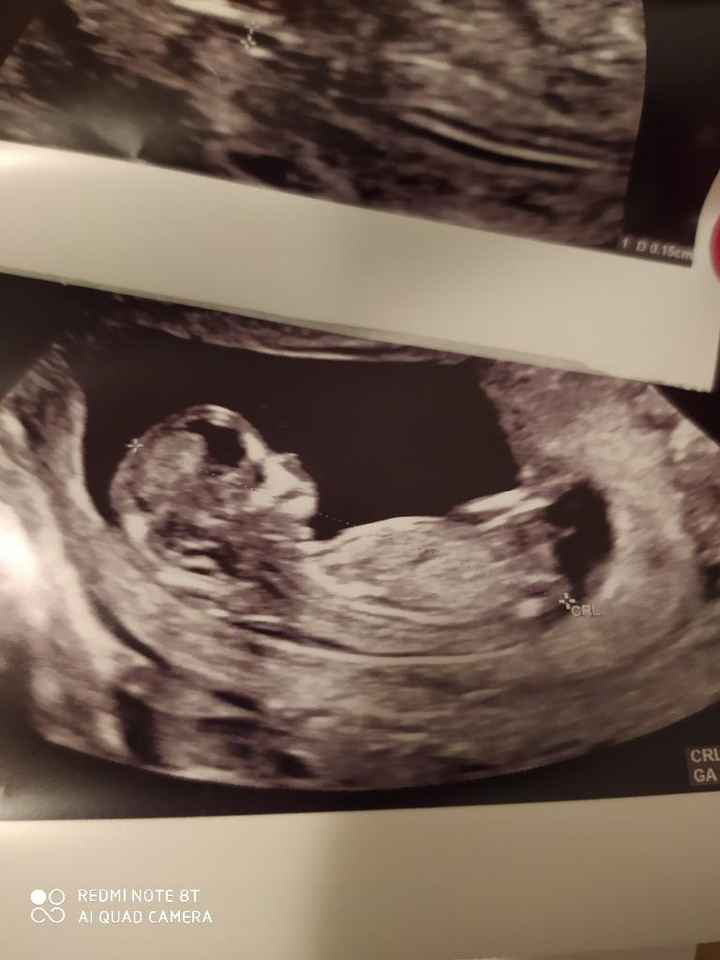

Buongiorno ragazze, secondo voi cosa aspetto? Il medico ha lanciato una scommessa su femmina! Voi che dite?Nub theory 3